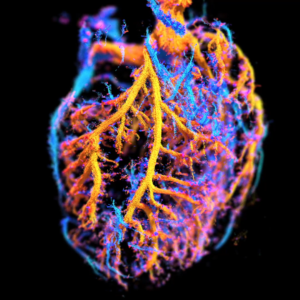

The coronary microcirculation was imaged in the beating heart using 3D ultrafast ultrasound localization microscopy.

Apr 15, 2022

The heart microcirculation captured in 3D using ultrasound microscopy